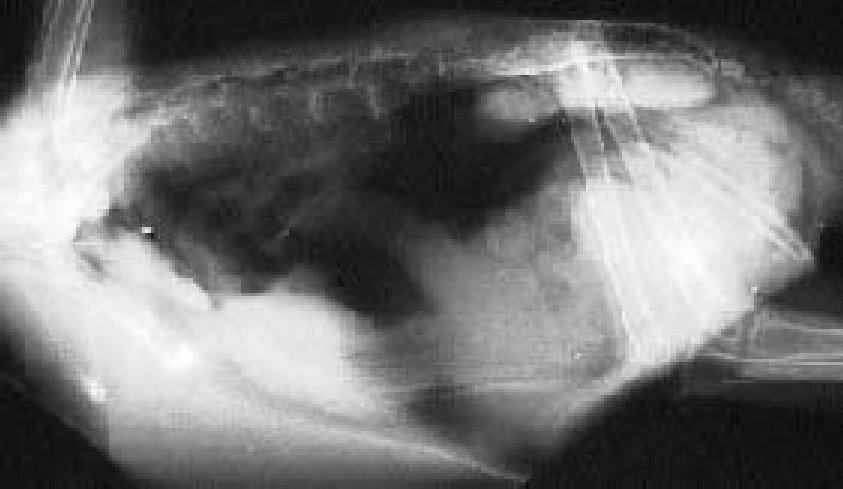

Tijdens zo een onderzoek wordt barium aan de vogel gegeven om het

spijsverteringsstelsel duidelijk te laten zien en om te zien of er geen andere

oorzaken zijn.

Op deze foto zie je de met barium gevulde krop uiterst rechts, er is barium in

de slokdarm (pijl in het midden). De spiermaag bezit ook barium (pijl uiterst

rechts), maar de vergrootte kliermaag heeft geen barium erin. De kliermaag kun

je zien juist links van de spiermaag.